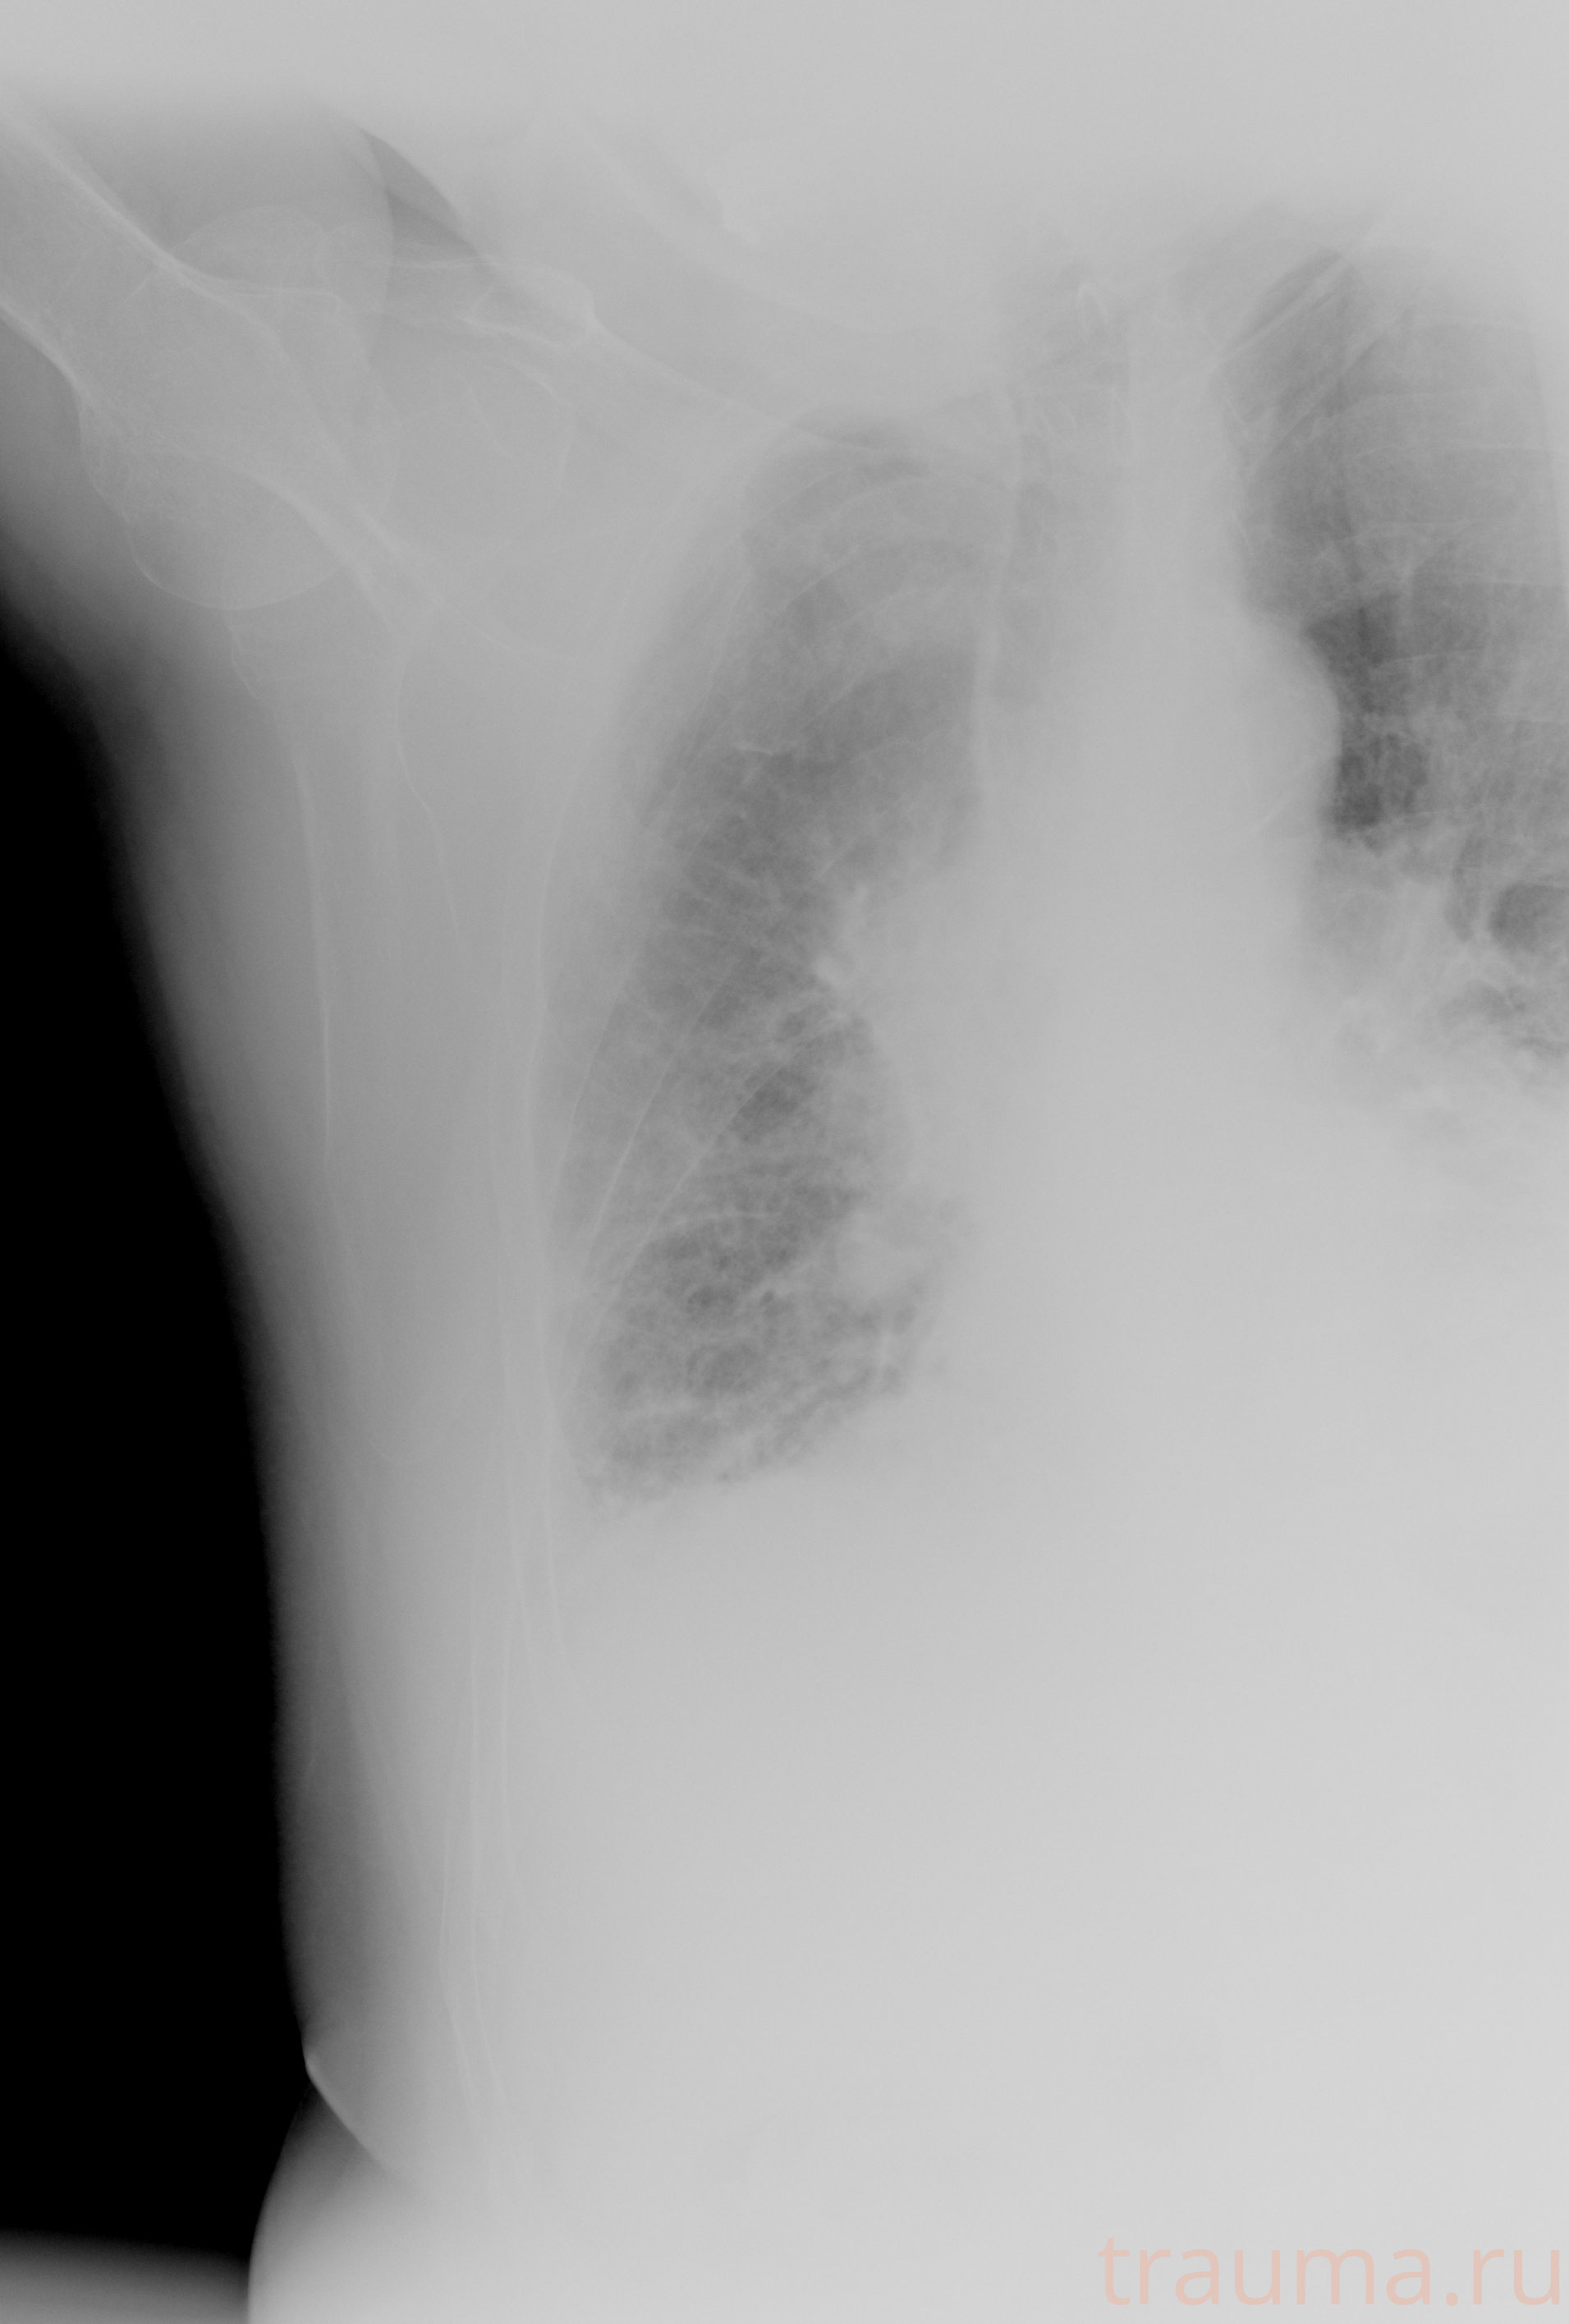

Рентген на дому: по вашему адресу приезжает врач-рентгенолог, травматолог-ортопед с мобильным рентгеновским аппаратом, проводит диагностику травмы или заболевания, делает необходимые рентгенограммы, дает рекомендации по дальнейшему лечению. Получить качественные снимки в домашних условиях возможно благодаря уникальной методике, разработанной МосРентген Центром для института  Склифосовского

при переломе шейки бедра и пневмонии от компании МосРентген Центр - партнера Института имени Склифосовского